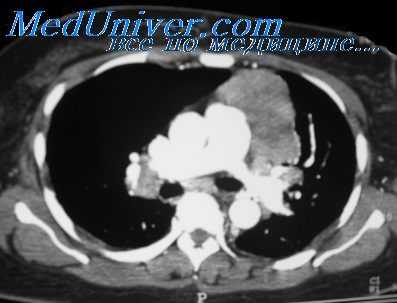

3. КТ тимомы:

• КТ с контрастным усилением:

о Мягкотканное объемное образование переднего средостения:

- Прилежит к верхнему краю перикарда и крупным сосудам

- Может располагаться на протяжении от верхней апертуры грудной клетки до кардиодиафрагмального угла

- Редко выявляется в других отделах средостения

о Обычно односторонняя локализация; развивается в одной доле тимуса

о Вариабельный размер

о Форма шаровидная или овоидная

о Четкий ровный или дольчатый контур

о Часто гомогенная структура

о Гетерогенный характер накопления контрастного вещества:

- Участки пониженной плотности, обусловленные некрозом или кровоизлиянием

- Кальцификаты:

Криволинейные, расположены на периферии вдоль капсулы или перегородок

Крупные или точечные

- Кистозные изменения: содержимое жидкостной плотности:

Мягкотканная капсула по периферии кистозной полости, узелок в ее стенке

о Обычно лимфаденопатия отсутствует

о КТ позволяет исключить местную инвазию жировой клетчатки средостения, сосудов, перикарда, сердца, плевры, легких

о Инвазивная тимома (30-60%):

- Облитерация клетчаточных пространств не исключает инвазии

- Частые признаки:

Зоны пониженной плотности, обусловленные некрозом опухоли

Контур опухоли дольчатый или неровный

Инфильтрация прилежащей жировой клетчатки

Множественные кальцификаты в структуре опухоли

Размер >7 см

- Непосредственные признаки инвазии:

Инвазия сосуда: неровный контур сосуда, его циркулярный охват, облитерация, опухолевый компонент в просвете сосуда

Узелок (узелки) в плевре: расположение одностороннее, двухстороннее, диффузное

Утолщение перикарда, его инвазия, узелки в нем

Вовлечение в опухолевый процесс легких: редко опухолевый компонент выявляется в просвете бронха

(а) У пациента с тимомой при КТ с контрастным усилением в преваскулярном отделе средостения определяется объемное образование, гетерогенно накапливающее контрастное вещество. Образование расположено в левой половине преваскулярного отдела средостения и прилежит клеточному стволу. Признаки инвазии сосуда отсутствуют. Отсутствие клетчаточных пространств при КТ органов грудной клетки не является надежным признаком местнодеструирующего роста.